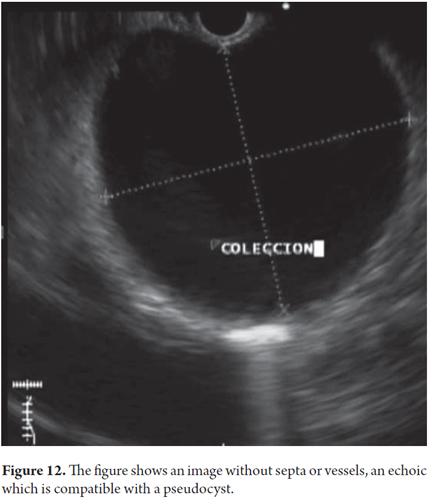

We will describe the technique we have been using in our service for about5 years. The patient is sedated by an anesthesiologist and is placed in left lateral position. Then we introduce the endoscope. Next, we find the pseudocyst (Figure 11) and the wall that separates it from the gastric lumen. We evaluate it by measuring its thickness and using a Doppler signal to rule out the presence of vessels (Figure 12). Once the site chosen has been located, we mark the area with biopsy forceps (or ink), then we remove the echoendoscope and replace it with a duodenoscope which we believe provides better angulation for drainage. After introducing a guided papillotome needle with coagulation current set at 30V, the wall is perforated (Figure 13). Once entry to the pancreatic pseudocyst has been achieved, the guide wire should be advanced guided by fluoroscopy (this is not strictly necessary: we have drained some cases in the endoscopy room). The coagulation hole can now be extended to 2 or 3 mm in diameter using the same papillotome for cutting (Figure 14). This will allow passage of the prosthesis (this step can be done with a biliary dilatation balloon, but it is more expensive). The papillotome is then removed and the prosthesis is advanced (Figure 15). Then the orifice is cannulated again, and - using the same method - we place the other prosthesis. Double pigtail 10 Fr type prostheses should be placed. For 5days following the procedure, 1.5 grams of ampicillin/sulbactam should be administered orally every 6 hours, and 1 tablet of fluconazole should be administered daily (8, 9). Because of the high rates of recurrence, prostheses should remain in situ for 8 weeks. At the point another CT scan should be performed. If there are no residual lesions, the prostheses should be removed (4).